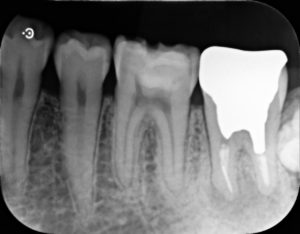

治療後

根管治療終了直後

今回の症例では根管内の汚染が強く、破折器具もはじめからしっかり見えたことから超音波切削器具と次亜塩素酸ナトリウム等を用いて除去しました。再度根管充填を行ったあと、病変の縮小をみとめた後に歯冠修復を行いました。